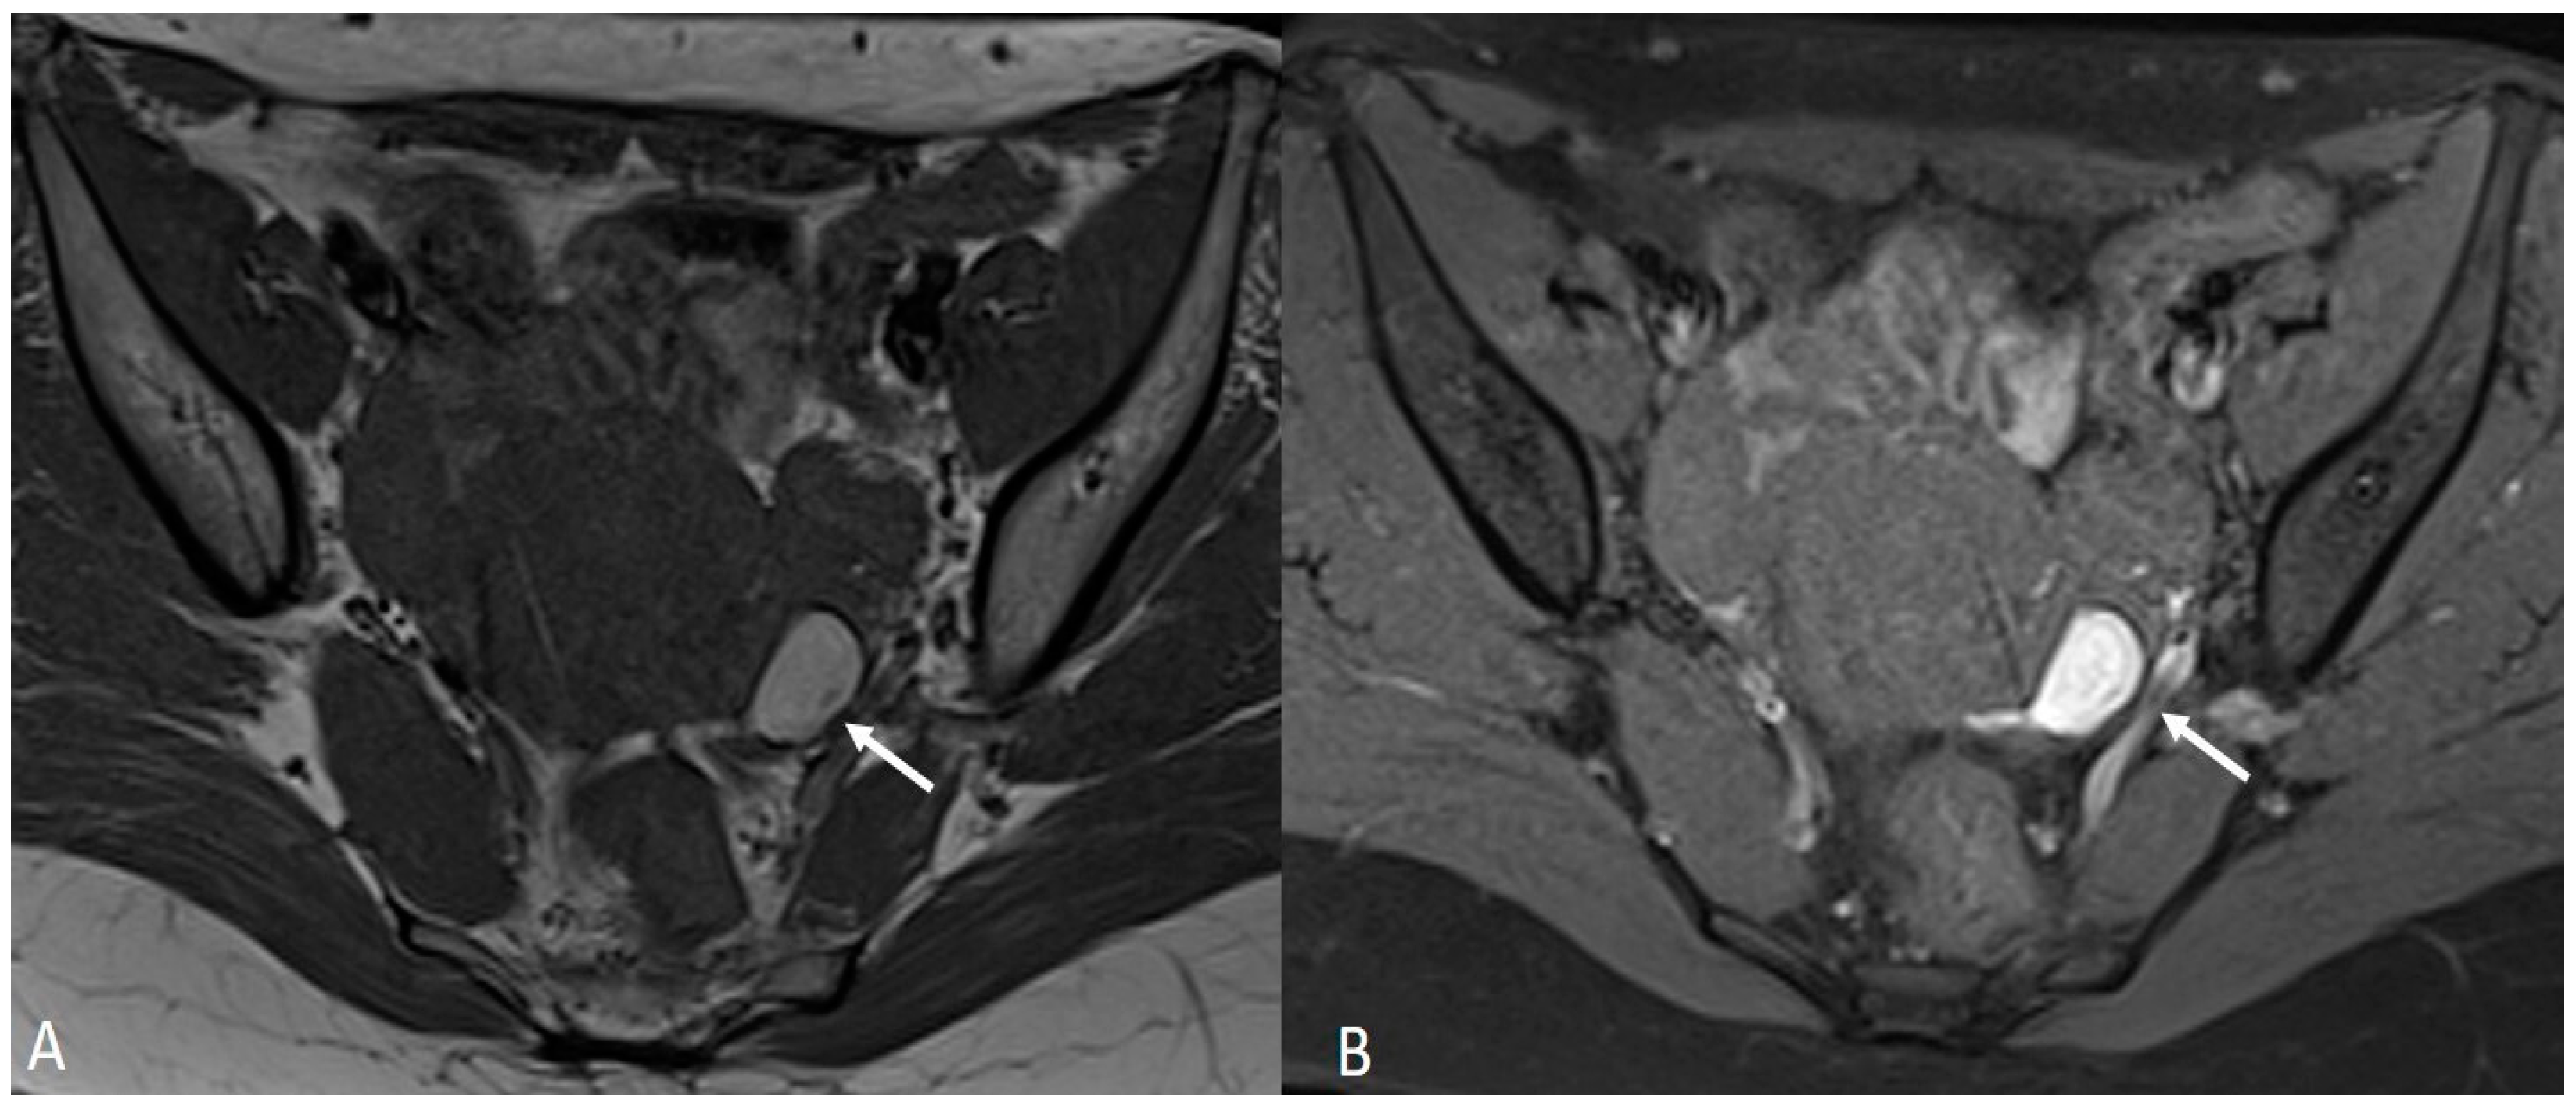

Generally, they appear hyperintense on fat-suppressed T1WI and T1WI (Figure 7 and Figure 8). The hyperintensity on fat-suppressed T1WI helps differentiate endometriomas from dermoid cyst and teratoma, which usually contain fat [51]. On T2WI, a variable signal can be obtained: a hypointense signal can affect variable portions of the cyst, sometimes also presenting a stratification, until a complete loss of the signal. This is called the shading sign and is correlated to the different state of hemoglobin degradation [52] (Figure 8). The T2 dark spot sign refers to hypointense spots in the wall of the cyst due to the presence of macrophages (Figure 9).

Figure 7.

Ovarian endometrioma in a 37-year-old female. (A) Axial T1WI; (B) Axial fat-suppressed T1WI. Typical aspect of an ovarian endometrioma (white arrows).